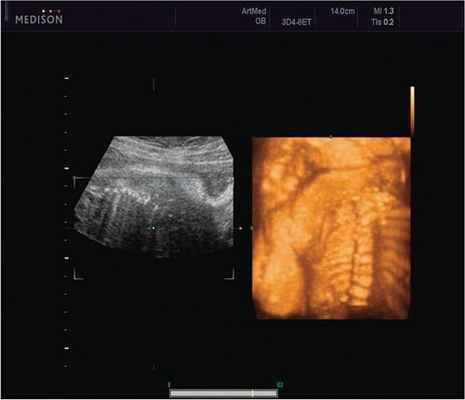

Пациентка К., 26 лет, обратилась в клинику в 23 нед беременности. Беременность первая. Исследование проводилось на аппарате Accuvix-XQ (Samsung Medison) с использованием режима поверхностной объемной реконструкции 3D/4D. Показатели фетометрии полностью соответствовали сроку беременности. В процессе сканирования позвоночника во фронтальной и сагиттальной плоскостях выявлена угловая деформация позвоночника в грудном отделе, протяженностью около трех позвонков. В поперечной плоскости сканирования нарушения структур и целостности тканей не было обнаружено. В режиме 3D/4D реконструкции было выявлено асимметричное расхождение ребер правой и левой стороны грудной клетки (рис. 4).

Рис. 4. Эхографическая картина асимметрии ребер в режиме 3D реконструкции.

Ребра левой стороны были сближены, межреберные промежутки уменьшены по сравнению с противоположной стороной (рис. 5, 6). Другой патологии у плода не было выявлено. Заподозрен врожденный сколиоз, основой которого является наличие боковых полупозвонков (hemivertebrae) или боковых клиновидных позвонков. В 26 нед ультразвуковая картина сохранялась. При проведении трехмерной эхографии получено отчетливое изображение асимметрии реберных дуг и сколиотическая деформация позвоночника.